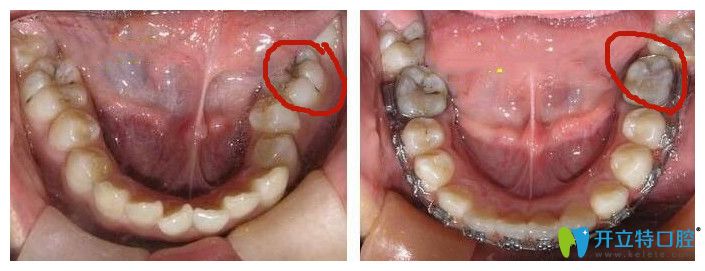

牙齒鎖合圖片

鎖合牙圖片